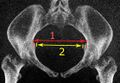

Размеры таза

Размеры и форма таза имеют важное значение для родового процесса и подлежат измерению и оценке у всех беременных. Для определения внешних размеров таза у живого человека пользуются измерительным инструментом — тазомером Мартина, внутренние размеры выясняются расчётными методами исходя из внешних, также применяется мануальное исследование через влагалище и ультразвуковые исследования, рентгенологические исследования, в том числе компьютерная томография, у беременных применяются в исключительных случаях для уточнения в виду нежелательного влияния ионизирующего излучения на плод и красный костный мозг женщины[1].

Размеры таза (в скобках у мужчин)[2]:

- Distantia interspinosa — между верхними передними подвздошными остями — 23-25 (21-23) см

- Conjugata anatomica или diameter recta (анатомическая конъюгата/прямой диаметр верхней апертуры) — между мысом крестца и верхним краем лобкового симфиза — 11,5 (10,8) см

- Diameter transversa (поперечный диаметр верхней апертуры) — наиболее отдалённое между пограничными линиями — 13,5 (12,8) см

- Diameter obliqua (косой диаметр) — между расположенными с противоположных сторон крестцово-подвздошным суставом и подвздошно-лобковым возвышением — 12,0-12,6 (12,0-12,2) см

- Прямой размер таза — между стыком II и III крестцовых позвонков и задней частью середины лобкового симфиза — 12,2 (10,8) см

- Поперечный размер таза — между центрами вертлюжных впадин — 11,5 (10,8)

- Прямой диаметр нижней апертуры — между вершиной копчика и нижним краем лобкового симфиза — 9,5 (7,5)

- Поперечный диаметр нижней апертуры — между седалищными буграми — 10,8 (8,1) см

- Угол наклона таза - угол между горизонтальной плоскостью и плоскостью верхней апертуры таза

В гинекологии и акушерстве, кроме упомянутых, имеют значение ещё следующие размеры таза[2]:

- Distantia intercristalis — между подвздошными гребнями тазовых костей — 25-27 см

- Distantia intertrochanterica — между большими вертелами бедренных костей — 28-29 см

- Conjugata vera (истинная гинекологическая конъюгата) — между мысом крестца и самой задней точкой лобкового симфиза — 10,5-11,0 см

- Conjugata diagonalis (диагональная конъюгата) — между мысом крестца и нижним краем лобкового симфиза — 12,5-13,0 см.